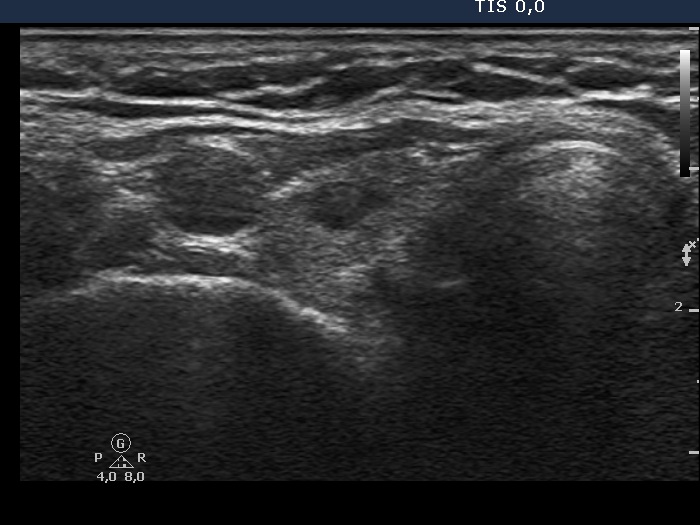

Rare forms of thyroiditis - Case 2: Acute purulent thyroiditis

30 month after the initial examination (ultrasonographic picture 1)

Right lobe, horizontal scan. There is a small hypoechogenic lesion in the right lobe.